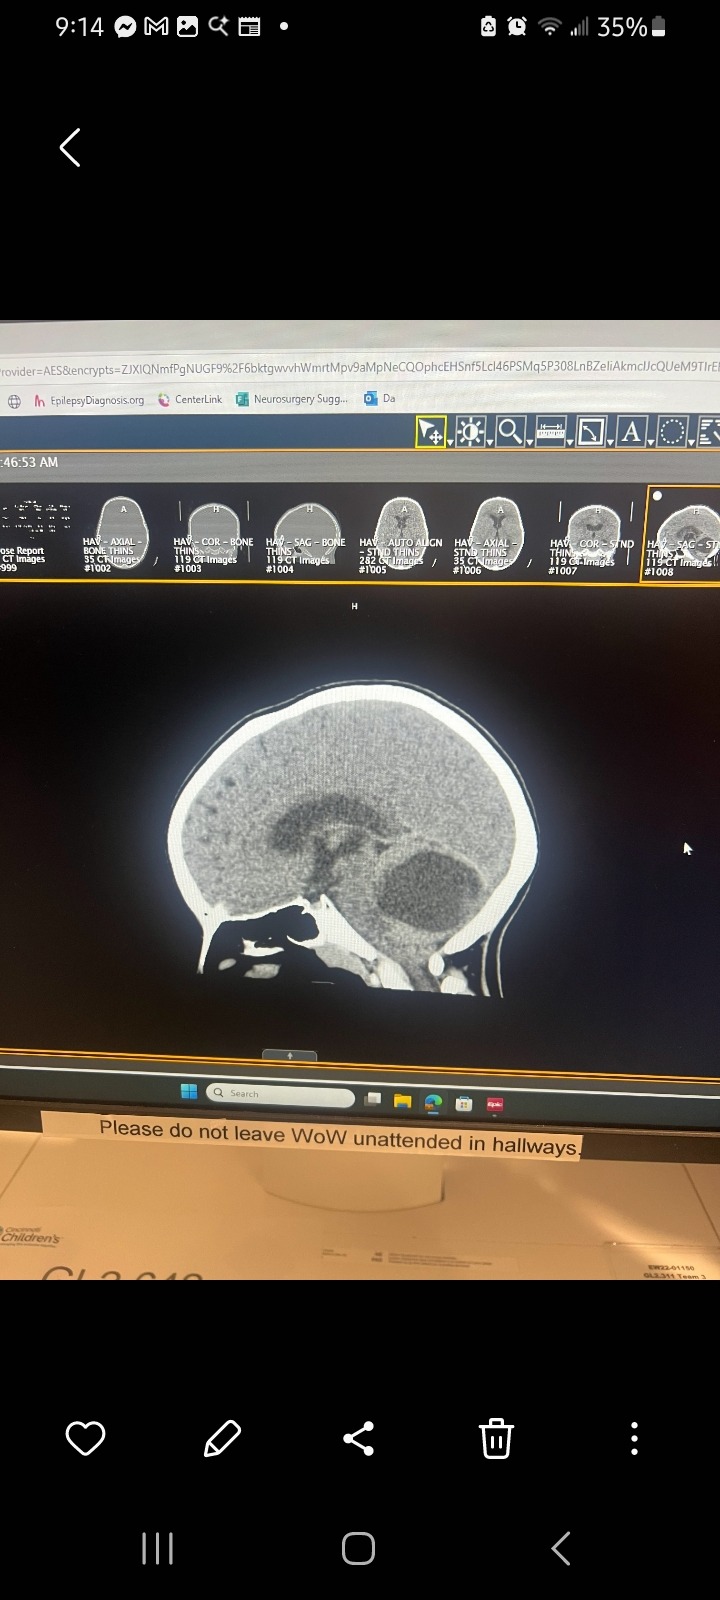

I'm fundraising for my friend January and her family. Recently, her youngest of 6. Ronomy, spent 3 weeks at a Norton's Children's and did not find answers. He was directly admitted into Cincinnati Children's and within the hour, they found out he has a large tumor/mass in his brain. Her and her husband are struggling financially and will for some time. If you find it in your heart to donate anything, they will be grateful. Please help this loving family overcome this most difficult life event. If you can't donate, please send healing energy, love, and prayers. Everything helps.

I'll update this as I learn more. Right now, he's in the OR having his first brain surgery.